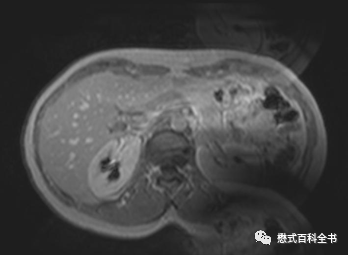

图10、11:打火花伪影表现

Spike伪影的表现还是比较典型的,一般称为电火花伪影。问了一下FSE工程师,这个伪影产生原因是,硬件系统不稳定,在采集信号的时候产生一些打火花,然后在图像上表现就是一条线状影。在整个采集信号的过程中,打了多少火花,可能就产生了多少条这种线状伪影。总结一下就是封闭磁体间内某些放电辐射导致斑马线伪影产生。

伪影表现主要为:覆盖整个图像的斑马线状伪影。可为单一方向,也可为多个方向相交排列。可出现在序列的某一幅图像中,也可出现在整个序列。

如果出现这种伪影,解决方案一般是:检查噪声滤波器;检查内部有无松动部件;检查内部电缆。最好的方法就是直接联系工程师。